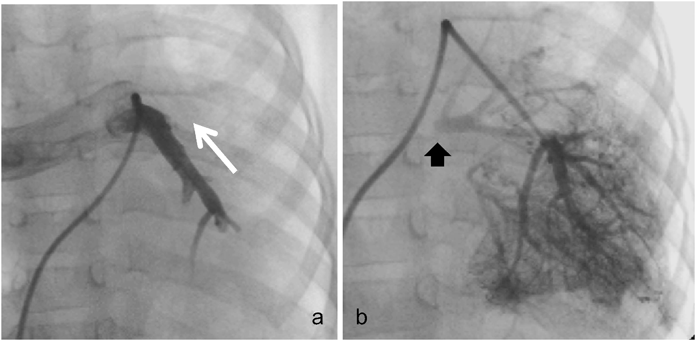

Fig. 6 Pulmonary arterial angiography in case 2

a) Left pulmonary artery flow was reversed in the right pulmonary artery. b) Left pulmonary arterial wedge angiography demonstrated the presence of a blind left pulmonary venous confluence (arrow).